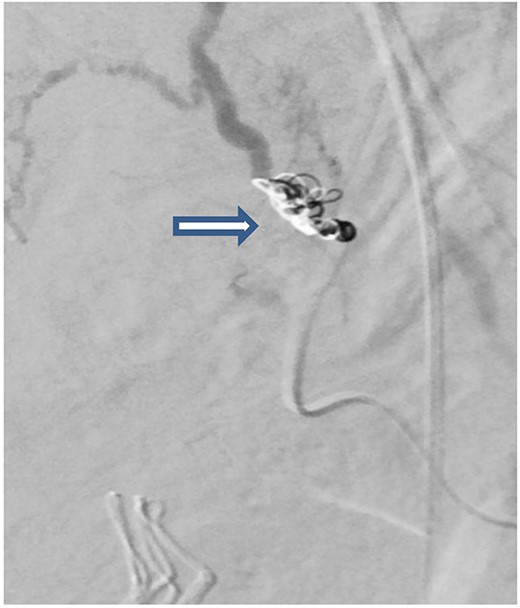

In total, 11 units of RBC, 12 units of fresh frozen plasma and 12 units of platelet concentrate, 6 units cryoprecipitate, Prothrombin complex concentrate (1000 units), fibrinogen (12 gram) and tranexamic acid were transfused (ROTEM-guided). The patient also received oxytocin (40 units) and methergine (0.4 mg) injections for the prevention and control of postpartum hemorrhage and then transferred to the hybrid operating room for imaging. Computed tomography (CT) scan revealed small laceration in the right lobe of the liver (segment 8) and another laceration at the upper pole of the right kidney without active bleeding. However, there was a focus of contrast blush seen in the arterial phase at the right lateral side of the uterine wall, which increased in the venous and delayed phases suggesting active arterial bleeding (Fig. 1a–c). The contrast extravasation is also seen within the endometrial cavity (Fig. 1c). Interventional radiologist was consulted, and he advised for close observation because these findings could be related to immediate postpartum uterine changes. The patient was transferred to the Trauma Intensive Care Unit (TICU) under mechanical ventilation, where she was hemodynamically stable. The last Intra-operative lab work showed hemoglobin level of 10 g and base excess was improved from −16 to −9 mEq/l. For completion of secondary survey, right shoulder X-ray was done and revealed a fracture of the right humerus head (Fig. 2). Few hours after admission to the TICU, the patient had post partum hemorrhage as frequent changing of blood-soaked packs was required and the hemoglobin dropped from 10 to 7 g. Sweeping of the uterine cavity was done by the obstetrician and small pieces of membranes was removed and no placental tissue was felt. Oxytocin drip 20 units in 500 ml was given intravenously and misoprostol 600 mcg was given rectally.

CT scan of the pelvis (a-c) after cesarean section revealed focus of contrast blush seen in the arterial phase at the right lateral side of the uterine wall, which increased in the venous and delayed phases suggesting active arterial bleeding. The contrast extravasation is also seen within the endometrial cavity.

The case was again discussed between trauma and obstetric teams for possible need for interventional radiology consultation. Angiogram showed tortuous arteries with parenchymal blush in the right side of uterine wall, which was related to postpartum status. Gelfoam embolization of the right uterine artery was done to reduce the flow. On the other side, angiogram detected a pseudoaneurysm measuring ~7 mm (Fig. 3). Multiple vortex coils were used to obliterate the feeding vessels and post embolization angiogram showed satisfactory results (Fig. 4).

Pelvic angiogram revealed a pseudoaneurysm (see arrow) measuring ~7 mm arising from the branches of the left uterine artery.